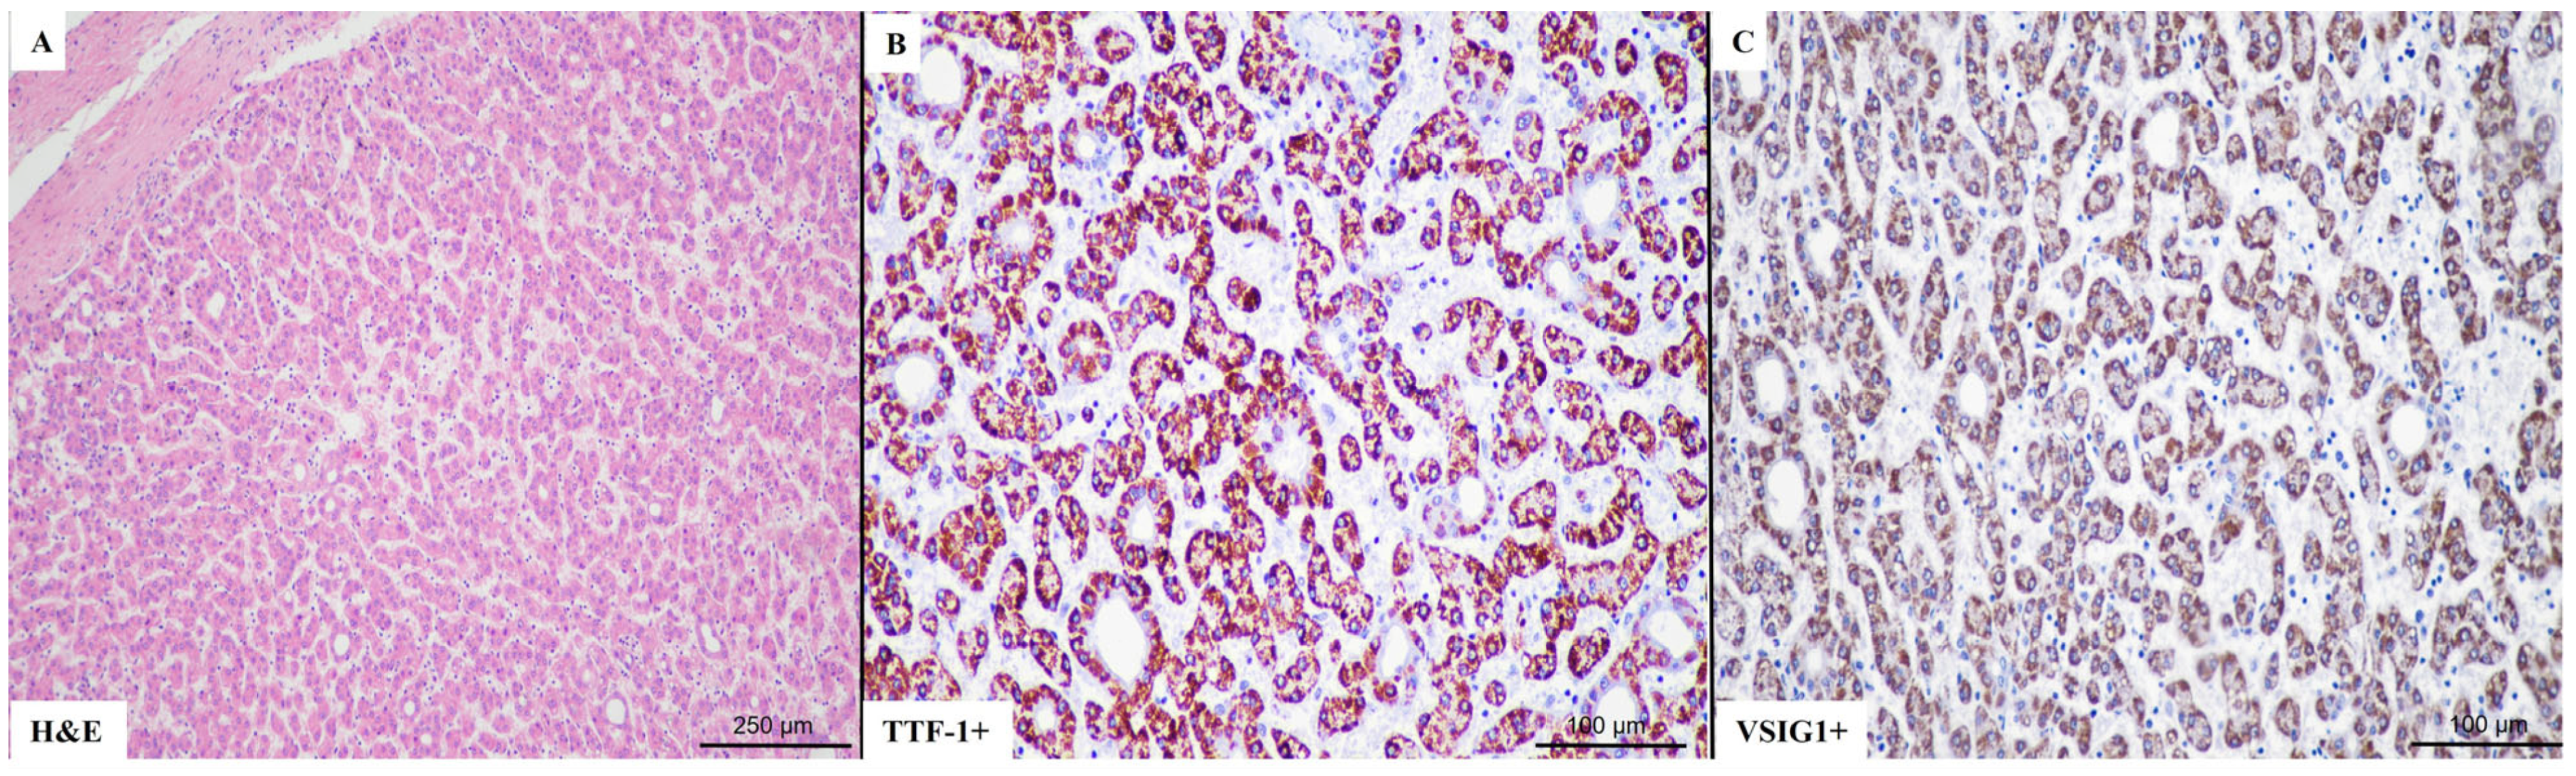

2.2. VSIG1 Correlation with Clinicopathological Parameters

2.3. TTF-1 Correlation with Clinicopathological Parameters